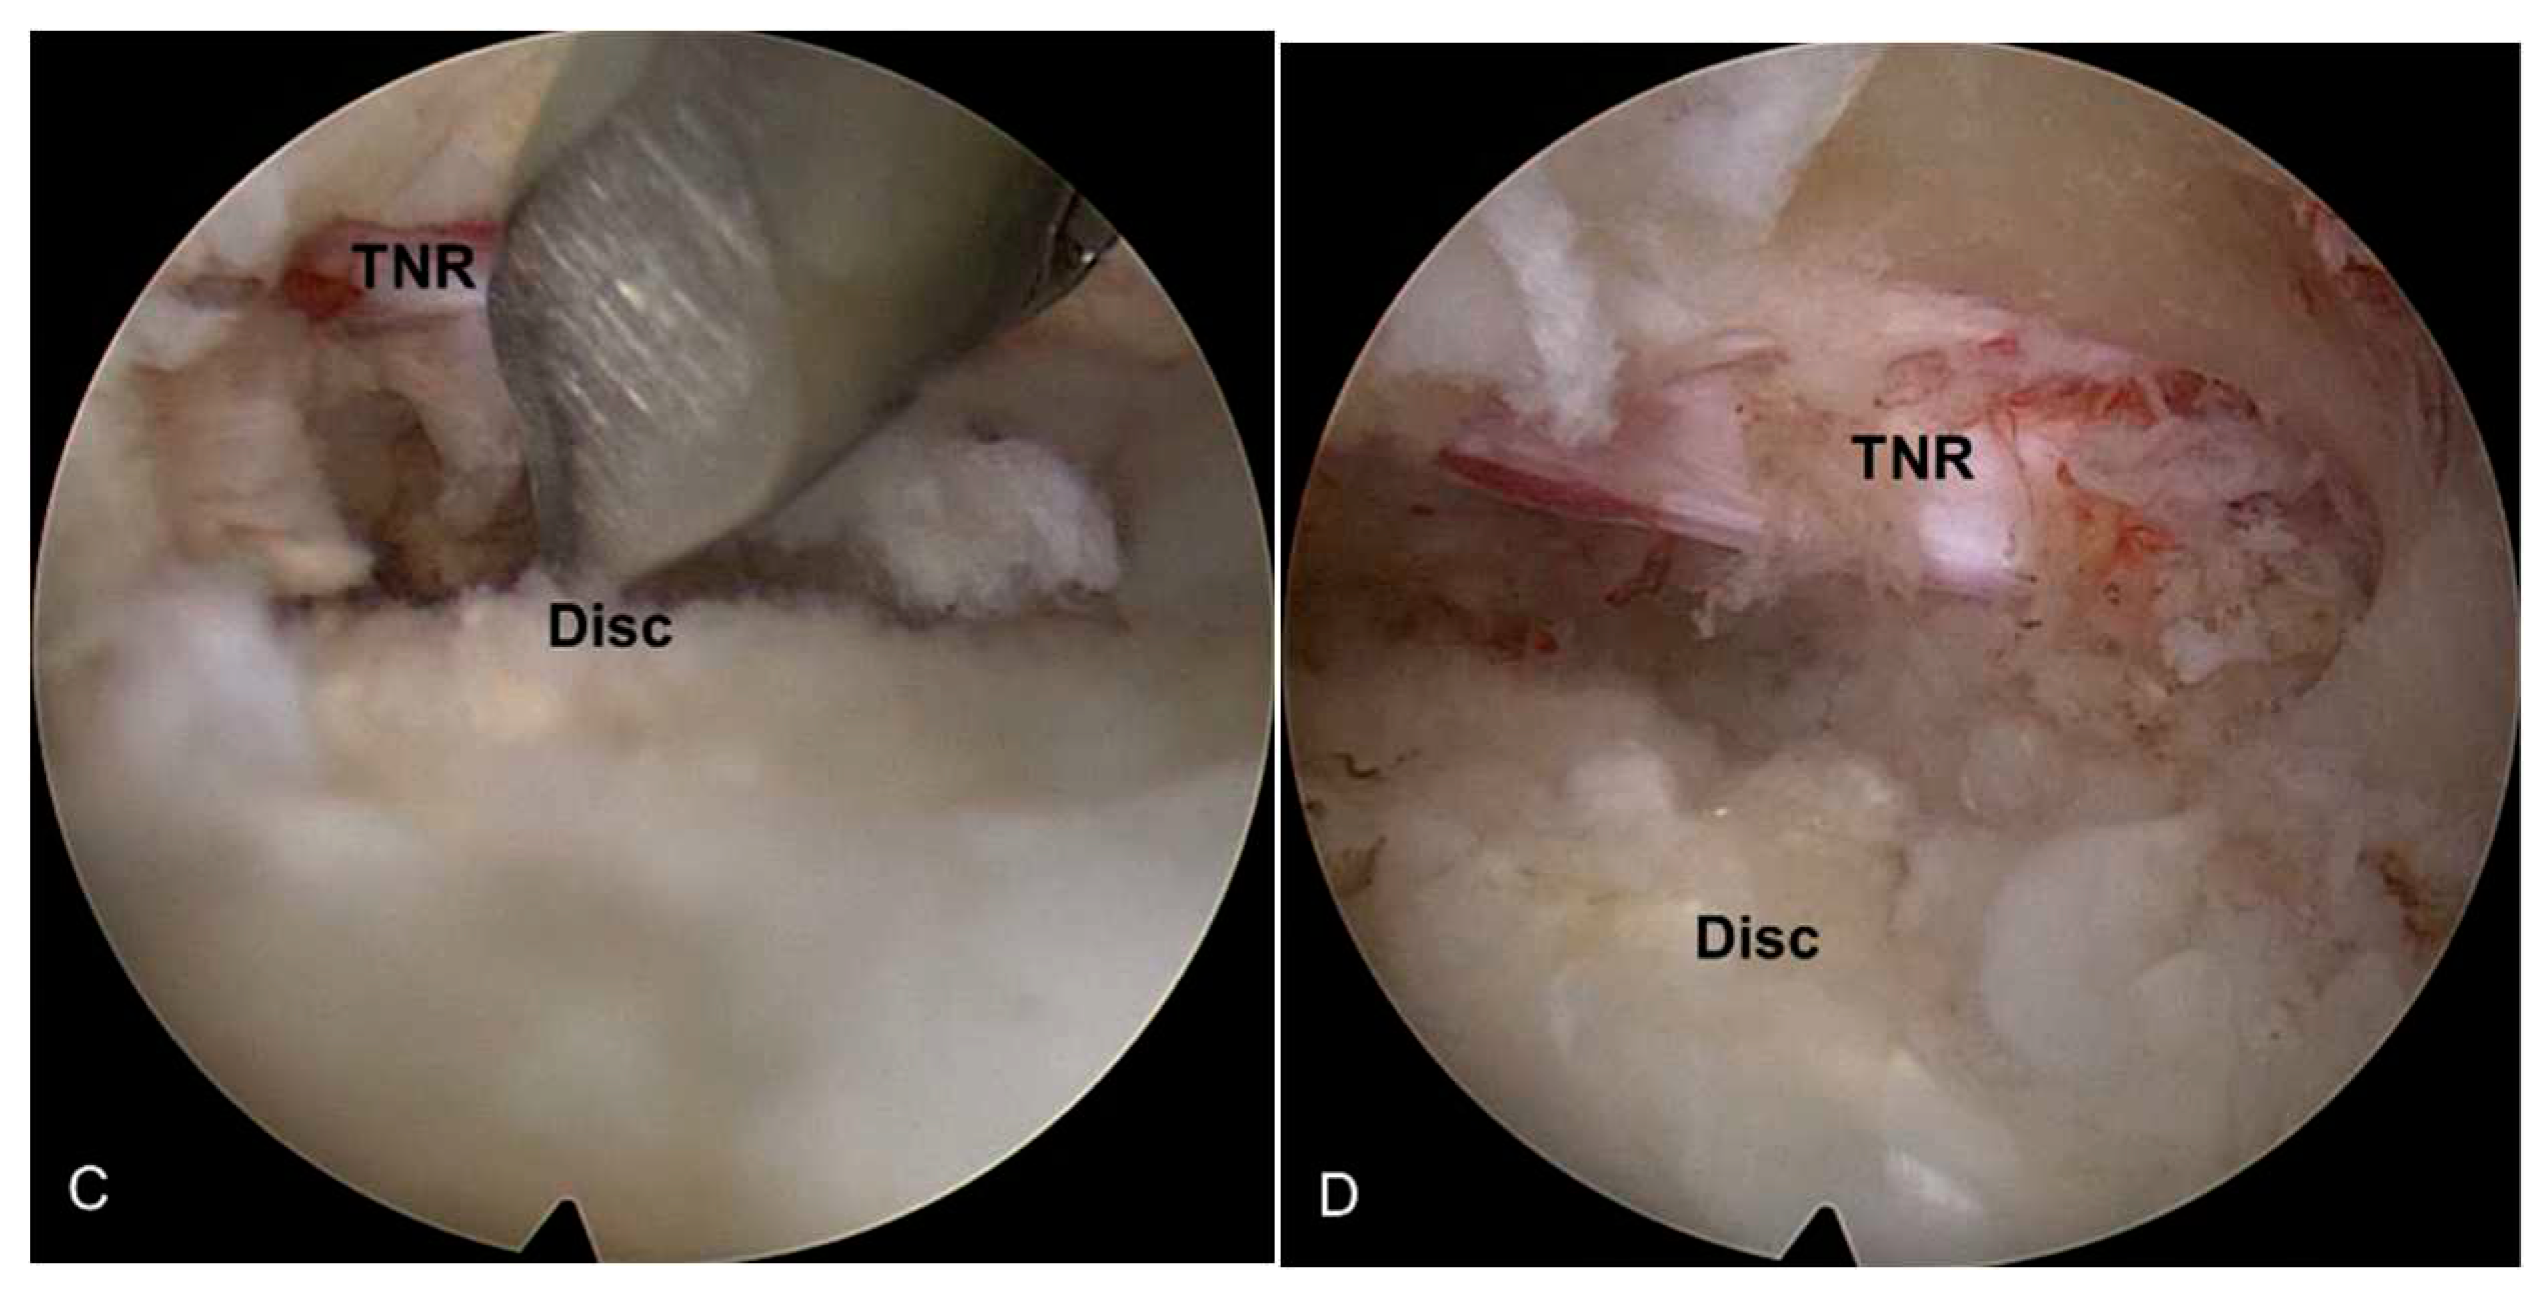

2.2.3. Endoscopic soft tissue decompression

After adequate lateral bony unroofing and widening, soft tissues such as thickened LF, redundant disc, and shoulder osteophyte were removed to alleviate compression on the TNR. Dorsolateral decompression was initiated by removing the hypertrophic LF with micropunches, small Kerrison punches, and semiflexible forceps with steerable RF coagulator tips. As the LF was gradually removed, the TNR and dural sac were also exposed. The decompression process required delicate tissue dissection under endoscopic visualization, and hydrostatic irrigation pressure was employed to aid dissection between the LF and neural tissues. The TNR was released from the axillary portion to the level of the inferior pedicle (Figure 2B). After sufficient dorsal decompression, a ventral decompression was performed. The shoulder osteophytes and redundant discs were removed using micropunches and burrs. The working sheath and endoscope were further advanced into the epidural space ventral to the dural sac. As the decompression progressed, the TNR became exposed and released (Figure 2C). This ventral work can be gradually performed from the lateral side to the midline, even to the contralateral side, as required. At this point, the surgeon can also encounter epidural or bone bleeding that interferes with the surgical field, which should be controlled using RF and hemostatic agents.

2.2.4. The target point of the decompression

The endpoint of TELLRD was determined by identifying the released TNR with the dural sac from the axillary to the inferior pedicle level. Successful neural decompression was confirmed by observing the strong pulsation of the nerve in synchronization with the patient’s heartbeat and soft mobilization upon probing (Figure 2D). After adequate hemostasis, a sterile dressing was applied with a one-point subcutaneous suture. The patient was monitored for at least three hours to detect any adverse events and then discharged within 24 hours. When required, postoperative imaging studies were conducted for precise pathological assessment (Figure 3).

Figure 2. Intraoperative endoscopic pictures TELLRD. (a) Bony unroofing using endoscopic burrs and punches. The hypertrophic SAP and part of the pedicle were undercut using an endoscopic burr (L4-L5, left). (b) Ventral decompression with removal of thickened LF using endoscopic punches. (c) Dorsal decompression with removal of redundant disc and shoulder osteophytes using endoscopic burrs and punches. (d) Final endoscopic view showing the released TNR. TELLRD, transforaminal endoscopic lumbar lateral recess decompression; SAP, superior articular process; LF, ligamentum flavum; TNR, traversing nerve root.